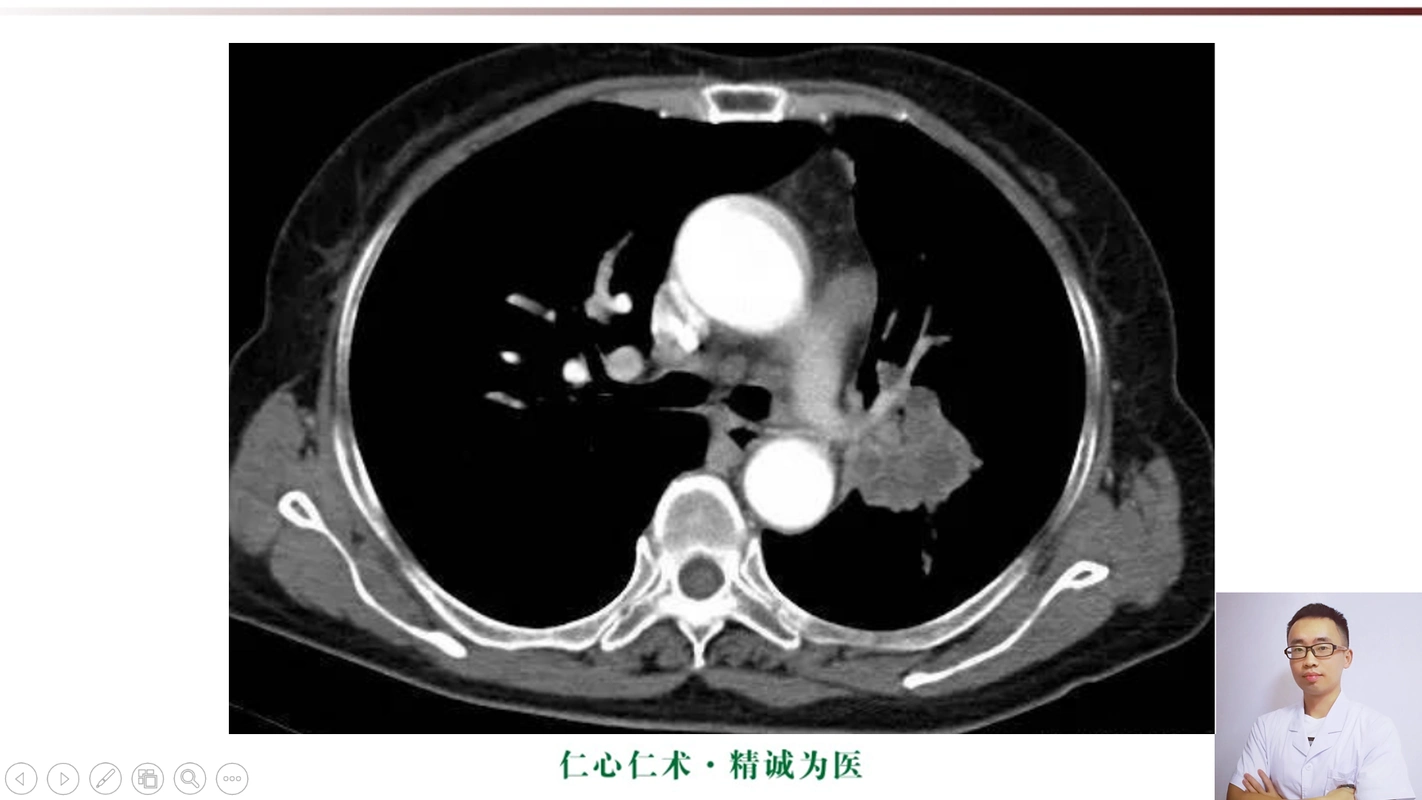

中央型肺癌ct

简述中央型肺癌特点及影像表现

在ct上,肺癌按照发生部位可以分为以下3种类型: 1,中央型肺癌:指肿瘤

影像基础知识:中央型肺癌ct表现及报告书写!

中央型肺癌一例直接征象和间接征象都有哪些